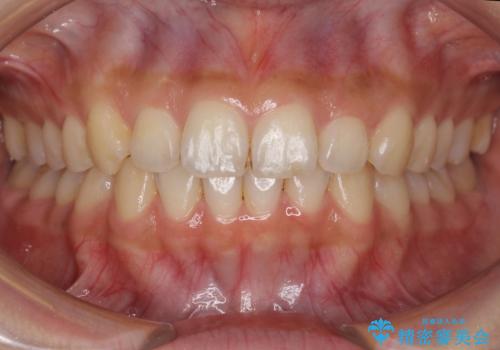

犬歯のねじれ 下の歯のがたがた インビザラインで

- 右上の犬歯のねじれ、下の歯のがたつきを主訴に来院。

インビザラインで歯を抜かずに並べました。

初回:上顎16ステージ 下顎22ステージ

リファインメント: 上顎23ステージ 下顎20ステージ

下の前歯のがたがたがそれなりにあったため、リファインメントを行いました。